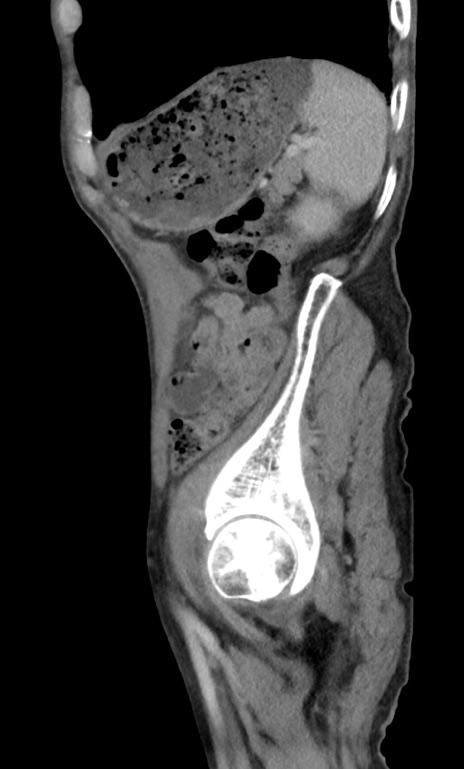

症例3(矢状断像)

【症例】 70歳代男性

【主訴】右鼠径部腫瘤、疼痛

【現病歴】本日朝より上記主訴あり、受診。

【既往歴】膀胱癌にて膀胱全摘、両側尿管皮膚瘻

【データ】WBC 5600、CRP 0.56